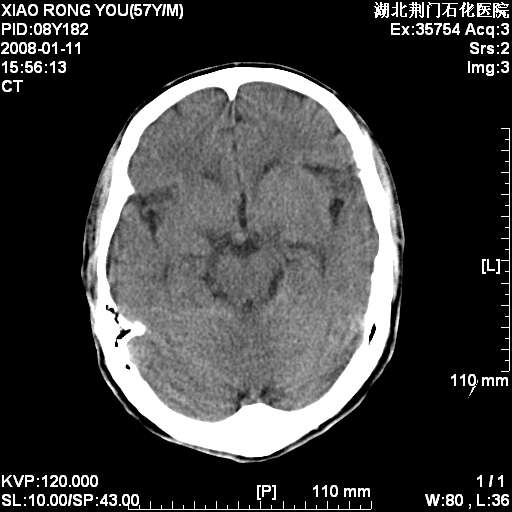

男性,68岁,多年肺结核病史。最近ct复查右肺有占位。

头部平扫